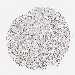

BRCA TCGA BRCA VALIDATION PROTEIN EXPRESSION

ANTIBODIES

AND

VALIDATION